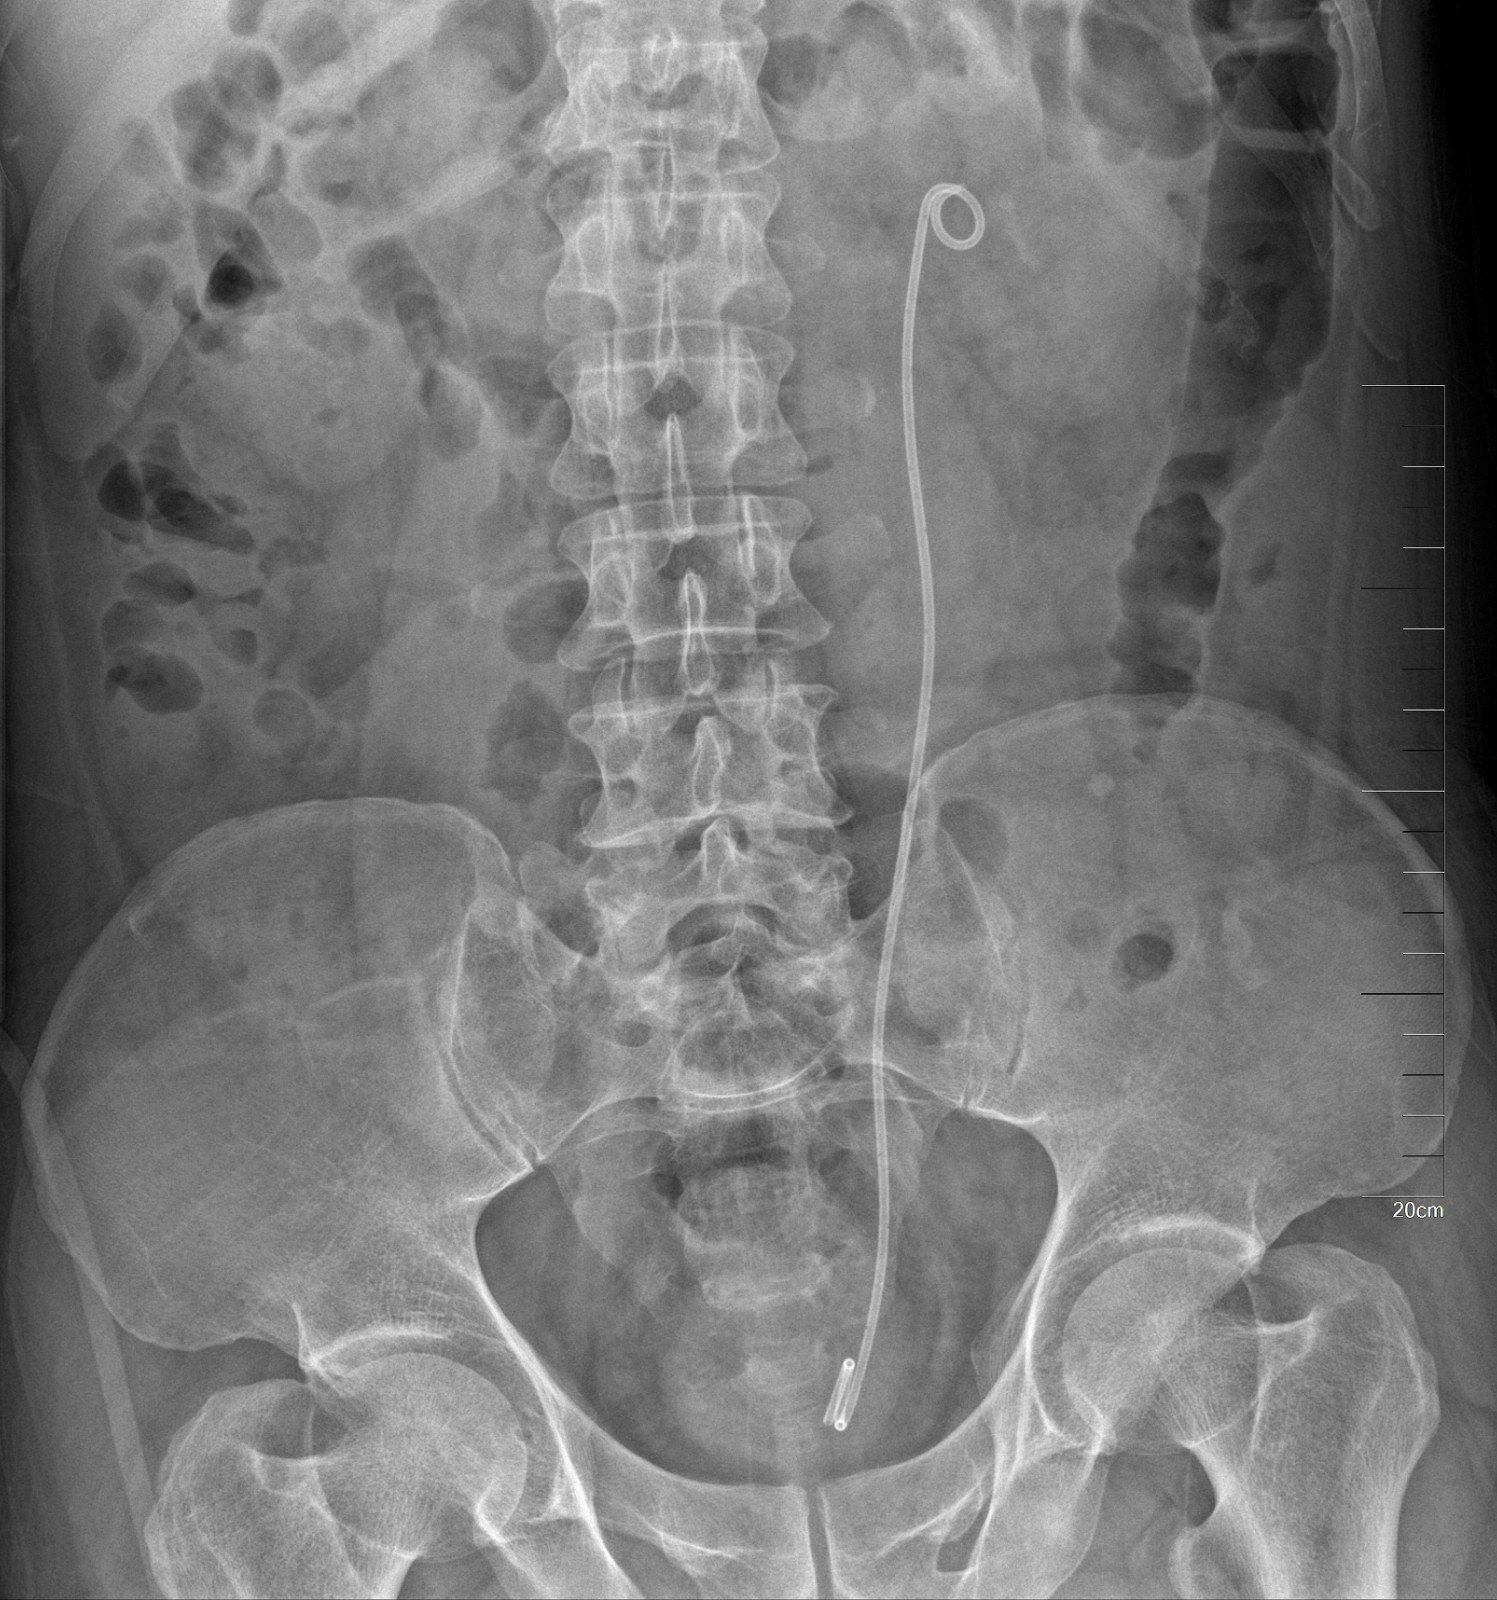

术后KUB见双肾造瘘管,及双侧内支架管固定妥善

正常人输尿管长约25cm左右,该患者输尿管迂曲扩张,长达35-40cm左右,裁剪部分输尿管成型